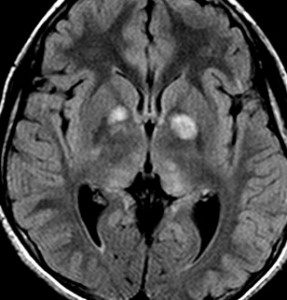

- 脳のところどころに,T2/フレアで何か特定できない高信号がみえます (UBO unidentified bright objects あるいはFASI focal area of signal intensityといいます)

- 病理学的には,髄鞘空洞化(myelin vacuolization, altered myelination),過形成性グリオーシス(hyperplastic gliosis)いわれるものです

- 過誤腫(hamartoma),異形成(dysplasia, heterotopia),脳室上衣下結節(subependymal glial fibrillary nodue)などもあります

- MRIで腫瘍のようにみえますがそうではありません。T2強調画像で白く見えてガドリニウム造影されないのが一般的な特徴です

NF-1に見られる典型的なUBOです。白くにじむように見えるところが,両側の大脳基底核から視床に散在しています。脳幹部にも同時に見られることが多いです。もちろん治療の必用はありません。